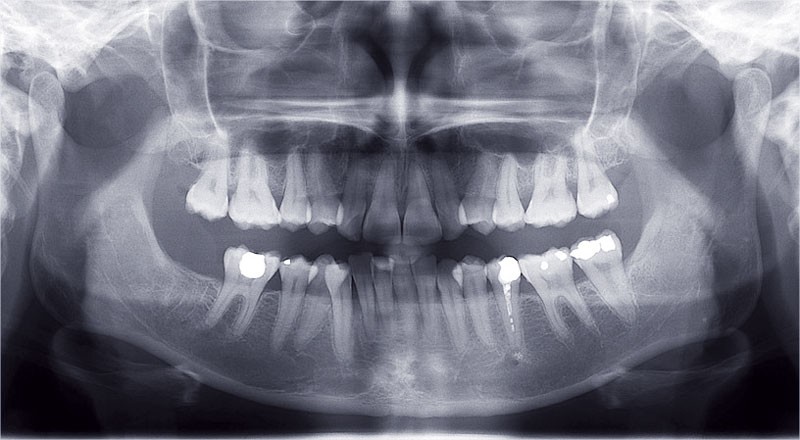

L’objectif, en utilisant la technique Insignia est de réduire le temps de traitement de 28 à 18 mois avec 12 rendez-vous (fig. 5 à 14).

Conclusion

Les objectifs de traitement ont été remplis. Nous avons observé un excellent contrôle du torque et une absence de perte de l’occlusion postérieure grâce à la technique Insignia.